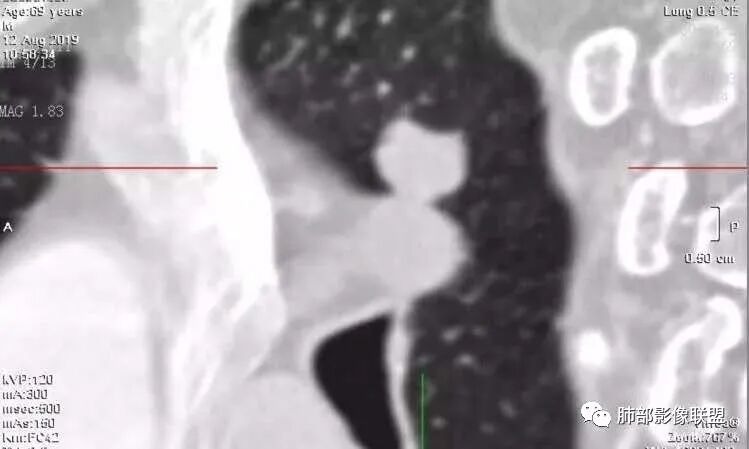

2.病灶的胸膜牵拉线与其间病灶胸膜侧的磨玻璃边构成朝向胸壁的“月牙铲”结构,这种影像学表现某种程度上反映出病理学特征——病灶收缩+小叶间隔阻挡。

月牙铲

在影像上观察到肿块或磨玻璃结节一侧的内凹,像个月牙铲形态,病理是肿瘤生长受到小叶间隔阻挡并受肿瘤内部的收缩力形成,王兆宇老师称之为“月牙铲”!对诊断肺腺癌较有特异性。